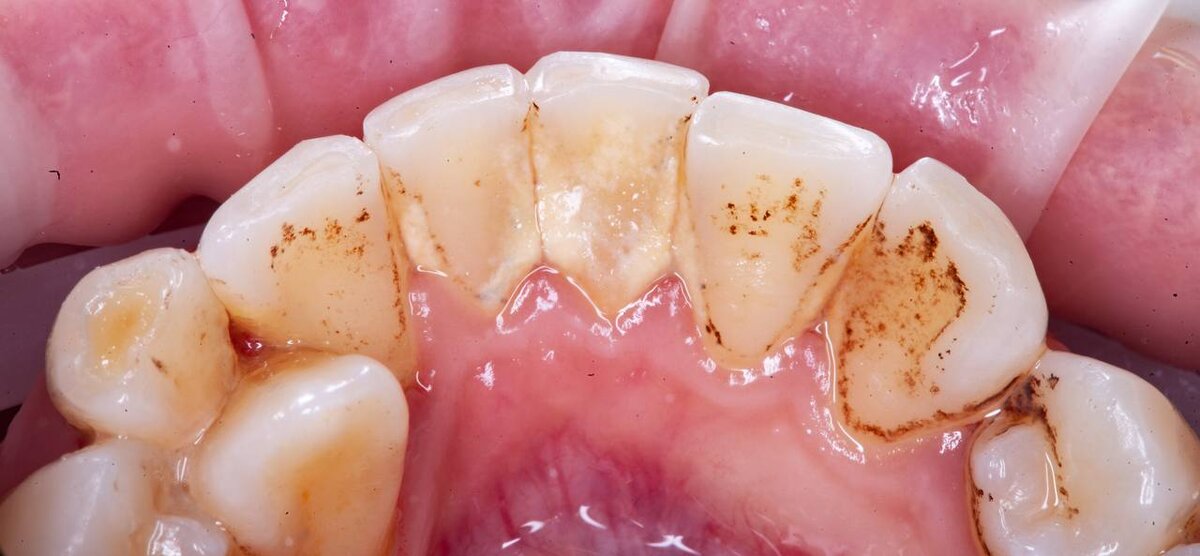

Эта фотопротокол - необходимый для стоматолога , чтобы наглядно показать пациенту отель проблемах в полости рта , а так же для проведения сравнения с результатом процедуры.

На данной фотографии, фото после проведения процедуры проф. гигиены. Фотографии из личного архива пациентов , не взятый из интернета. Наглядный пример «до» - «после».